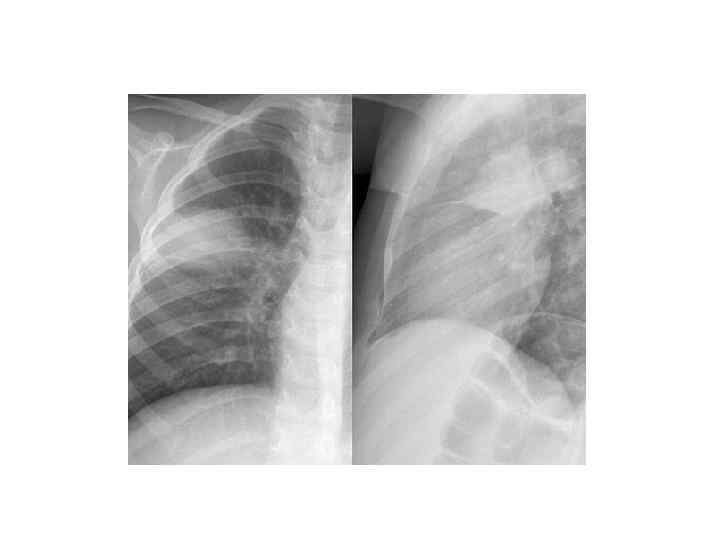

Рентгенологическая диагностика ВП • Рентген ОКГ является обязательным методом подтверждения диагноза пневмонии • Рентген ОКГ в двух проекциях должен быть проведен быстро при клиническом подозрении на пневмонию • Рентгенологический признак пневмонии – появление очаговой инфильтрации в легких

Показания к компьютерной томографии • При очевидной клинике ВП отсутствуют изменения в легких на рентгенограмме • Сложные диагностические ситуации • Затяжная пневмония (нет разрешения инфильтрата более 4 недель) • Рецидив пневмонии в той же доле